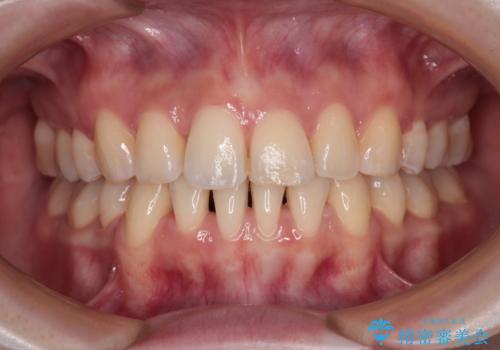

- 口元の閉じにくさを気にして来院された患者様です。

上下ともに歯列が前方に突出していたため、上下左右の第一小臼歯4本を抜去し、ワイヤー装置による矯正治療を行うこととしました。

舌の突出癖による影響もあったため、舌のトレーニングを並行して実施しました。

舌の突出癖がなかなか改善されず、上下前歯の接触がやや甘い状態での仕上がりとなりました。

接触が甘い場合、上顎前歯の叢生が後戻りを起こしやすくなるため、治療終了後の保定期間でも舌のトレーニングを継続するように指示しています。